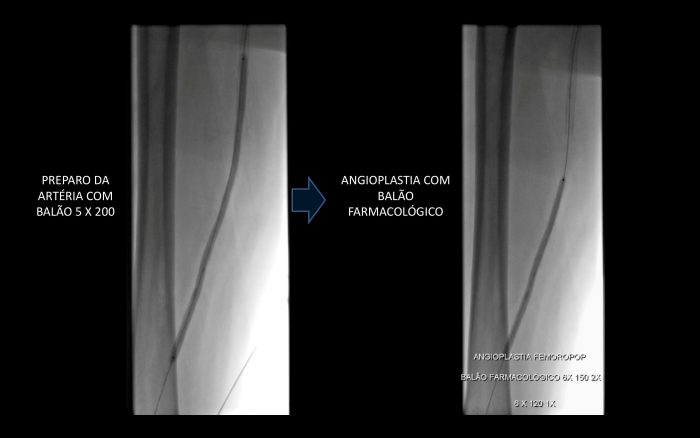

Paciente com história de claudicação dos membros inferiores para curtas distâncias, já submetido a angioplastia do membro inferior direito, retorna ao serviço com piora dos sintomas no lado esquerdo, sem lesão trófica (Rutherford 3)